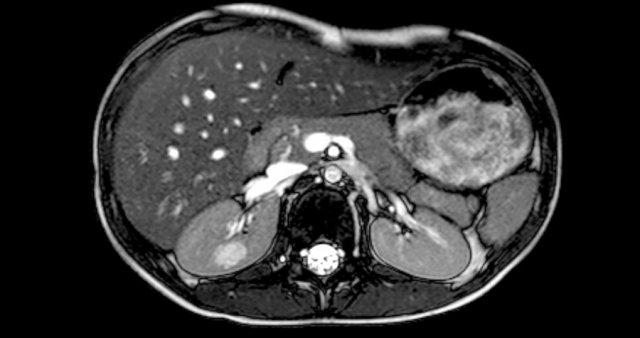

Một bé trai 7 tuổi được khám sau khi đái ra sỏi thận.

Trong quá trình siêu âm, phát hiện một khối u đa nang.

Sinh thiết cắt bỏ không lấy hết được tổn thương.

Trong 5 năm theo dõi, tổn thương ổn định, không thay đổi.

Trên MRI, tổn thương có ranh giới không rõ và có tín hiệu tương đương nước trên tất cả các chuỗi xung.

Hình ảnh này phù hợp với u thận nang (cystic nephroma).

Đây là hình ảnh của một bé gái 1,5 tuổi có khối u sờ thấy được ở bụng trái.

Siêu âm cho thấy một khối u lớn cấu thành bởi vô số nang, xuất phát từ thận trái.

Trên ảnh MRI mặt phẳng trán chuỗi xung T2W, các nang được hiển thị rõ ràng.

Phần còn lại của thận trái nằm ở phía đuôi của khối u.

Kết quả giải phẫu bệnh xác định là u nguyên bào thận dạng nang biệt hóa một phần.